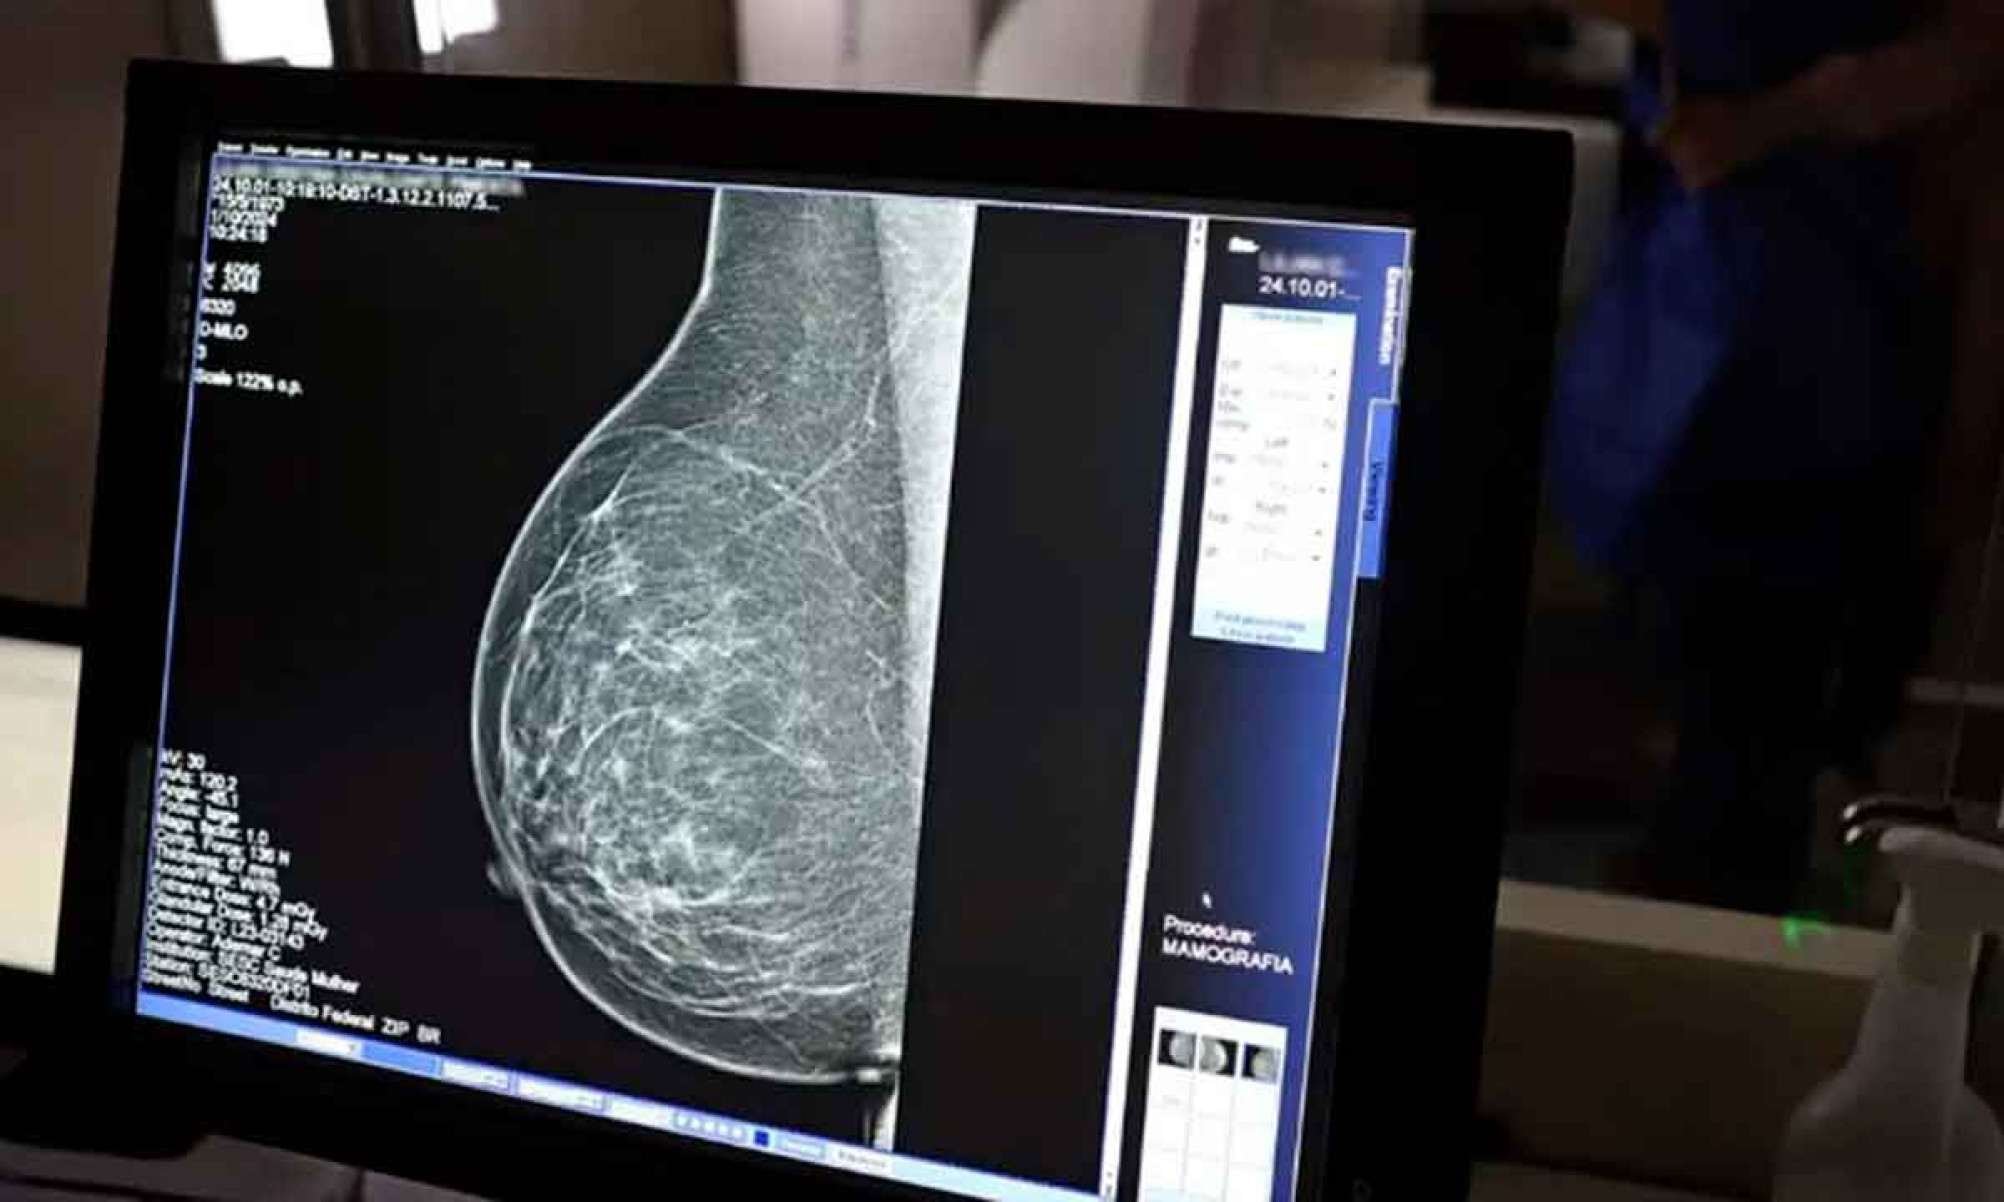

Um estudo publicado no BMC Women’s Health Journal - coordenado por professoras do Departamento de Enfermagem Materno-Infantil e Saúde Pública da UFMG -, revelou uma queda significativa na cobertura de mamografias em Belo Horizonte entre 2007 e 2023.

O índice, que chegou a 86,5% em 2012, despencou para 70% entre 2021 e 2022, o menor percentual registrado no período. Em 2023, houve leve recuperação, com 80,3%, mas ainda distante dos níveis ideais. A mamografia é essencial não apenas para o diagnóstico precoce, mas também para reduzir a mortalidade por câncer de mama, a segunda doença que mais mata mulheres no país, atrás apenas do câncer de pele não melanoma. O exame está disponível gratuitamente pelo SUS, garantindo acesso universal e contribuindo para a prevenção e o controle da doença.